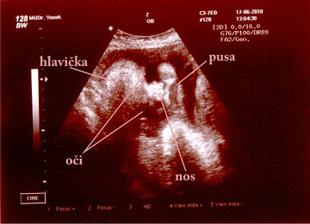

Náš malý Velký Zázrak - na světě II.

Jakub roste jako z vody 🙂 tak hlavně ať je pořád zdravý a má se dál k světu.

25. črc 2010